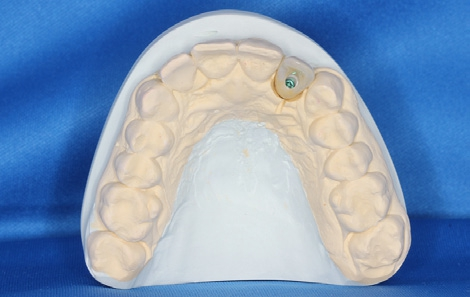

Zwei Wochen nach der Freilegung erfolgte die Abformung des Implantatsitus mit einem PEEK-Abformpfosten für die offene Löffeltechnik. Vorbereitend mussten die Klebebrücke und deren Überschüsse an den Nachbarzähnen entfernt werden (Abb. 21 und 22). Im Labor wurde ein PEEK-Implantatanalog mit dem Abformpfosten verschraubt und die Abformung ausgegossen. Das Meistermodell wurde einartikuliert und die Hybridabutmentkrone hergestellt. Das anatomische Kronendurchtrittsprofil wurde auf dem Gipsmodell angezeichnet und das Profil im subgingivalen Anteil der Versorgung mithilfe einer Fräse bis hin zum Laboranalog ausgeschliffen (Abb. 23). Die Abutments beim CERALOG Hexalobe Implantat sind aus dem innovativen Hochleistungspolymer PEKK (Poly-Ether- Keton-Keton) hergestellt. PEKK wird schon seit vielen Jahren in der Medizin eingesetzt – beispielsweise für kraniomaxillofaziale (CMF) Anwendungen in der rekonstruktiven Schädelchirurgie oder an der Wirbelsäule. Das Material ist sehr stabil und hat dämpfende Eigenschaften [19].

Das Abutment wurde im Labor modifiziert, eingescannt und eine okklusal verschraubte, anatomisch reduzierte Hybridkrone virtuell darüber designt. Im CAM-Verfahren wurde eine Zirkoniumdioxidkrone gefertigt, die dann bukkal verblendet wurde (Abb. 24). Durch die prothetisch orientierte Implantatpositionierung kam der Schraubenzugangskanal palatinal zu liegen. Die exakte Weichgewebsausformung durch das stabilisierende subgingivale Kronenprofil ist für eine langzeitästhetische Rekonstruktion essenziell.